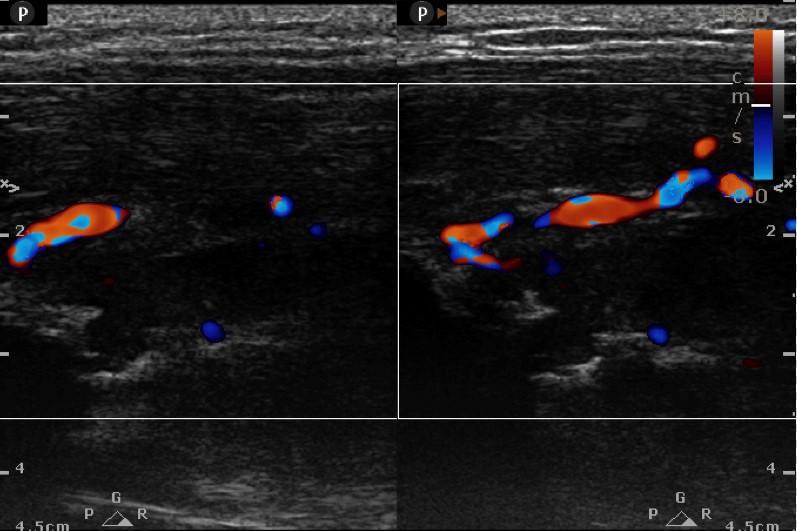

High frequency Ultrasound ( L12-5 MHz) (within 10 minutes of patient skigram): Increased thickness of belly of triceps. On CDU, increase vascularity. Cortical breach as punched - out (*)erosive lesion measuring 4x3 mm in mid shaft posterolateral humerus with new bone formation(^) . No periosteal or juxta cortical fluid.

Ultrasound provisional Diagnosis: Fibroscarcoma. Advised Ultrasound guided Tissue Biopsy.